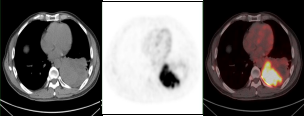

肺癌放疗前确定生物靶区:左肺下叶鳞癌患者(右图所示),左下肺癌病灶并远端阻塞性肺不张,PET/CT可以准确区分肿瘤组织与非肿瘤组织,确定肿瘤病灶生物靶区。